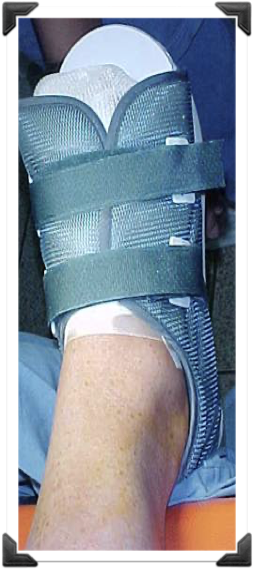

MANEJO ORTOPEDICO - NO ORTOPEDICO

4ta. Semana de Post-Operatorio